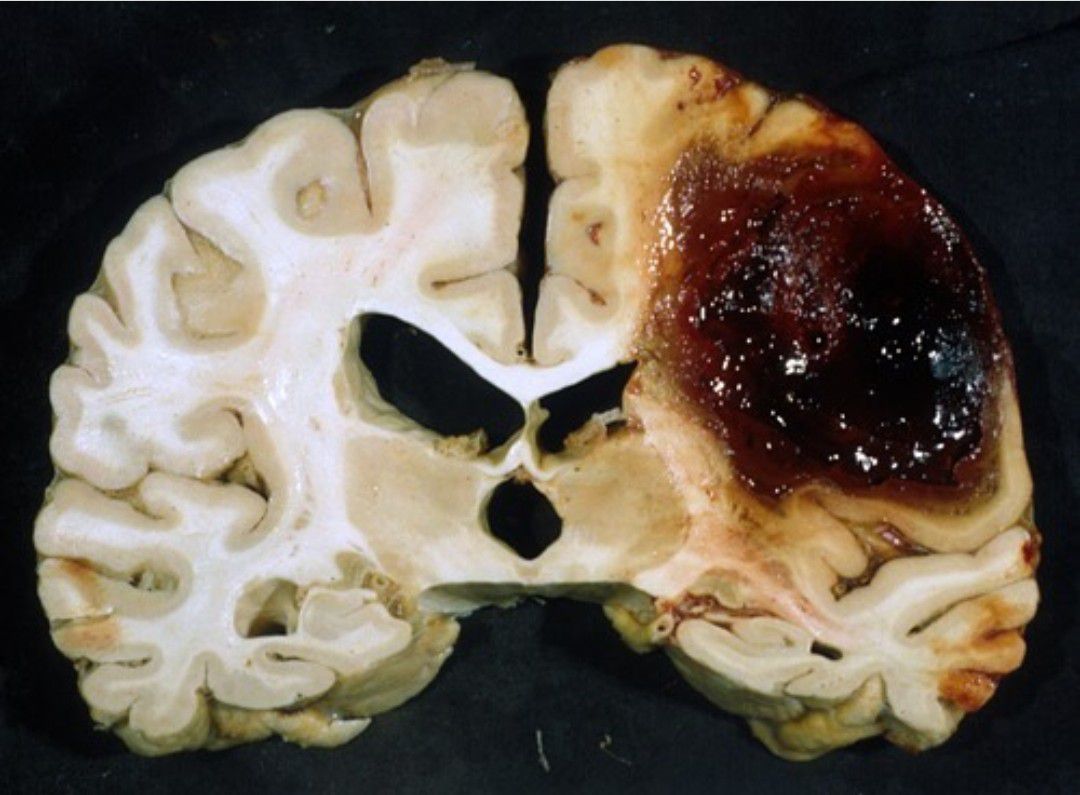

Lobar hemorrhage is a subtype of intracranial hemorrhage, which generally carries a poor prognosis. Primary lobar hemorrhages, usually due to cerebral amyloid angiopathy, are typically seen in elderly patients. Cerebral amyloid angiopathy (CAA), is a form of angiopathy in which amyloid beta peptide deposits in the walls of small to medium blood vessels of the central nervous system and meninges. Cerebral amyloid angiopathy increases the risk for stroke caused by bleeding and dementia.